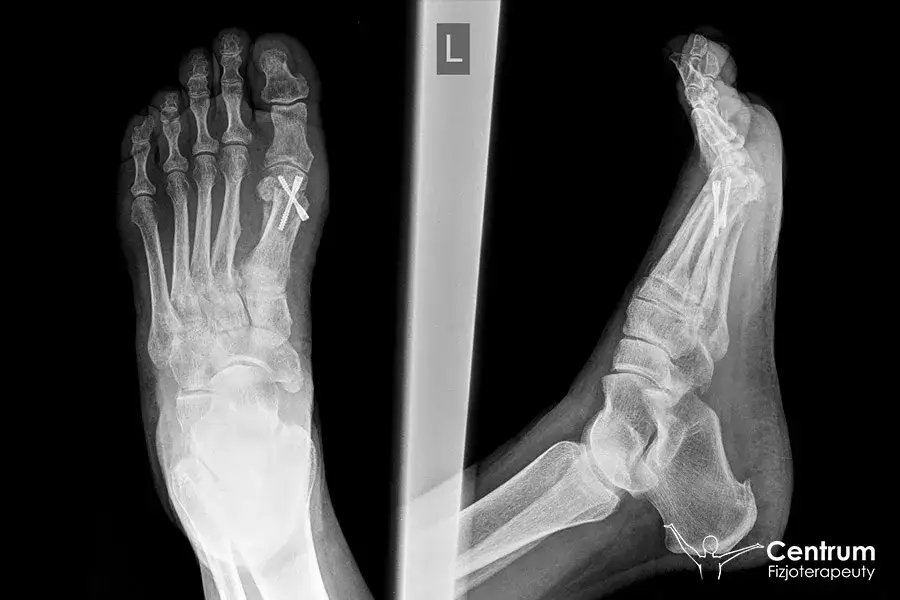

Po upływie około 6 tygodni od operacji nadchodzi moment przełomowy. Kluczowe jest wówczas wykonanie kontrolnego zdjęcia rentgenowskiego (RTG), które pozwoli lekarzowi ocenić, czy kości prawidłowo się zrosły. Jeśli obraz RTG potwierdzi sukces osteotomii, lekarz zazwyczaj zezwoli na odstawienie specjalistycznego buta pooperacyjnego. To sygnał, że możesz zacząć stopniowo wracać do noszenia normalnego obuwia i coraz śmielej obciążać operowaną stopę.

Decydujące zdjęcie RTG: Jak lekarz ocenia zrost kostny po 6 tygodniach?

Po około sześciu tygodniach od operacji wykonuje się kontrolne zdjęcie RTG. Jest to kluczowy moment diagnostyczny, podczas którego lekarz ocenia stopień zrostu kostnego w miejscu przeprowadzonej osteotomii. Analizuje się linię złamania, obecność tkanki kostnej wypełniającej ubytek oraz stabilność zespolenia. Pozytywny wynik, czyli potwierdzenie prawidłowego zrostu, jest podstawą do podjęcia decyzji o dalszym postępowaniu, w tym o możliwości odstawienia buta ortopedycznego i rozpoczęcia pełniejszego obciążania stopy.